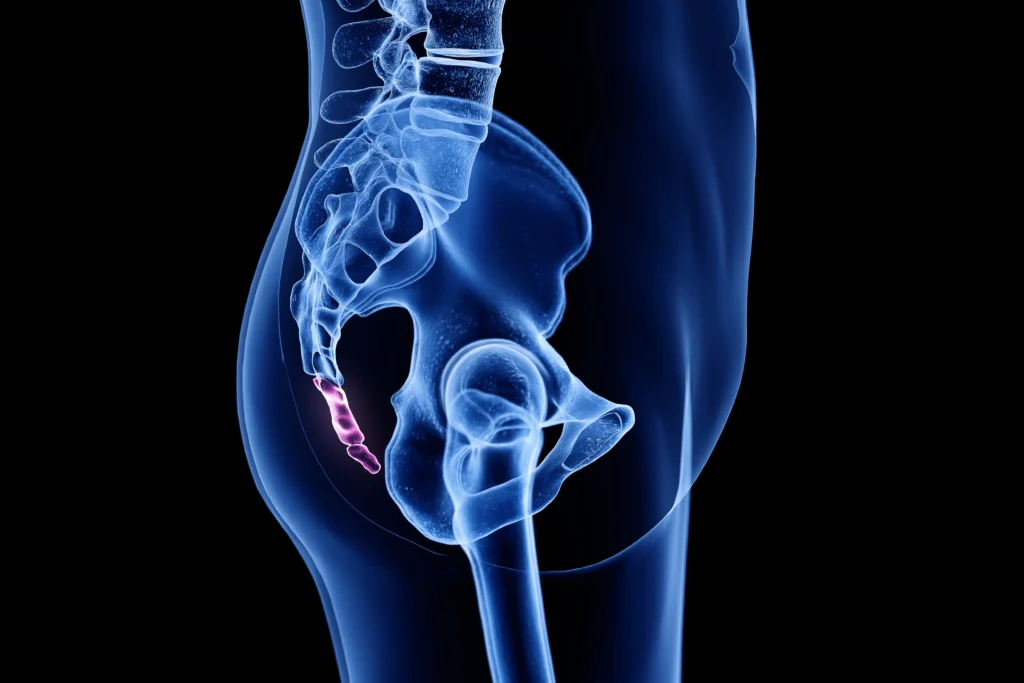

2-Kuyruklar

Gebeliğin altıncı haftasında, insan embriyosu birkaç omurla birlikte bir kuyruğa sahip oluyor. Ancak gelişimin sonraki birkaç haftasında kuyruk kayboluyor ve zamanla omurlar birleşerek yetişkinde kuyruk sokumunu veya kuyruk kemiğini oluşturuyor.

İnsanlar ve maymun akrabaları, kuyruksuzluklarıyla diğer primat gruplarından ayrılıyorlar; ancak maymunların kuyruklarını neden kaybettikleri belirsiz. Nadir durumlarda, bebekler körelmiş bir kuyrukla doğuyor. Modern tıp literatüründe, bu tür kuyruklarda omur yok ve genellikle zararsızlar; ancak bazıları spina bifida (omurların omuriliği tamamen kapatamaması) ile ilişkili. Bebeklerdeki kuyruklar genellikle komplikasyonsuz bir şekilde ameliyatla alınıyor.